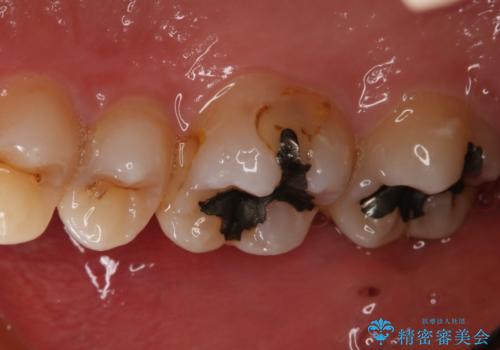

上はう蝕が歯頚部まで達していたのでクラウンでの治療を選択しました。

銀歯直下もう蝕が進行していたので全て除去した上でCRにて裏層しています。

下はクラウンほど切削量が多くないと判断し、インレーでの治療を選択しました。